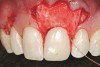

The 2.5-week postoperative clinical view can be seen in Figure 10 through Figure 12. Note the rapid soft tissue healing and maturation. At 6-weeks postoperative, tissue plasty was accomplished to blend the thickened keratinized tissue, in addition to placement of class V composite restorations at teeth Nos. 5, 6, and 11 to create a new restorative margin on the root surfaces.

The 2-month postoperative view can be seen in Figure 13 through 15. Note the color match of the tissue, balance of the facial heights of contour, and zones of attached keratinized tissue present.

Figure 12  Case One The 2.5-week postoperative view, maxillary left.

Figure 12